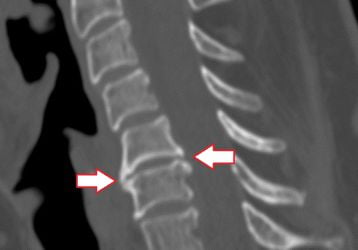

Данное поражение суставов является самым распространенным среди взрослого населения. Оно развивается у любого человека, независимо от возраста (может появляться не только у пожилых людей, но также и у молодежи), пола. Это целый комплекс дистрофических поражений хрящевой ткани. Болезнь имеет характерную особенность — она поражает чаще всего межпозвоночные диски.

Чаще всего это заболевание считается главной причиной появления болевого синдрома в спине. Впервые почувствовать развитие болезни можно уже в 20 лет. Далее, она очень быстро прогрессирует и становится только хуже. Боль является следствием того, что хрящ, который обеспечивает амортизационные свойства позвоночника, истончается. Диски сильно прижимаются друг к другу и поддаются трению, доставляя человеку дискомфорт.

3. Остеохондроз шейного отдела.